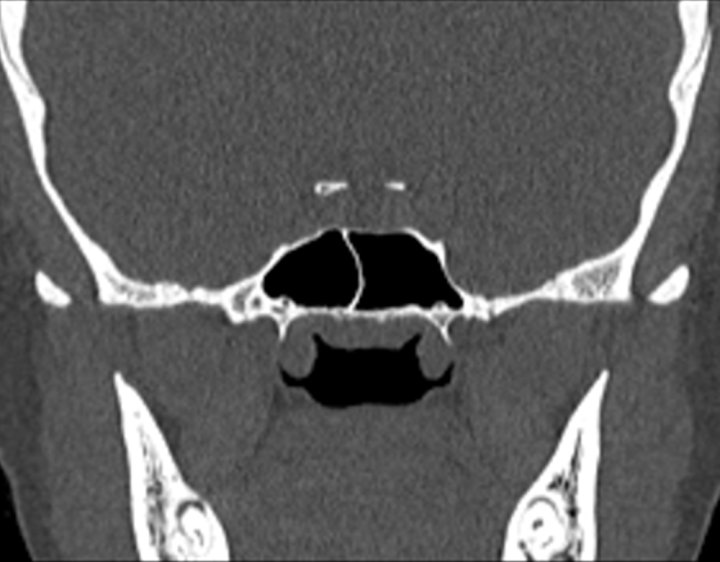

Click any image for labels.